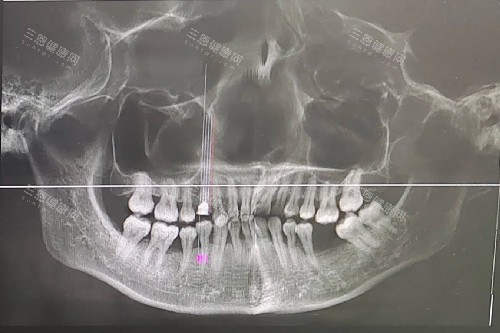

听医生说,麦芽的优势是医生团队:像郑苍尚院长做了10多年种植,李泓甫医生擅长智能化导板,术前用3D CT扫描,种牙位置更好到毫米。